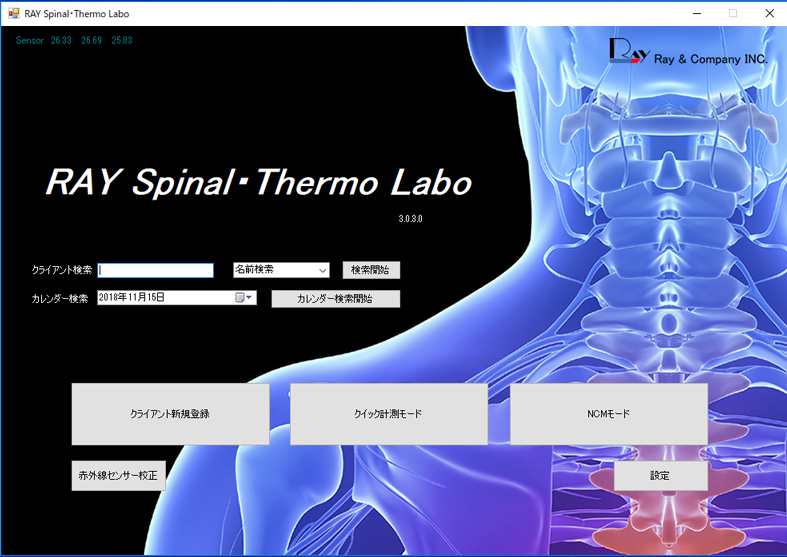

X線検査装置(CT) : 分析計測機器(分析装置) 島津製作所, 赤外線サーモグラフィ検査 - にしのカイロプラクティック院,

赤外線サーモグラフィ検査 - にしのカイロプラクティック院, SkyScan 1278 | Bruker,

診断用ソフト - dicomPACS® - OR Technology - Oehm und Rehbein, カイロプラクティック検査法| 姿勢分析

カイロプラクティック検査法| 姿勢分析